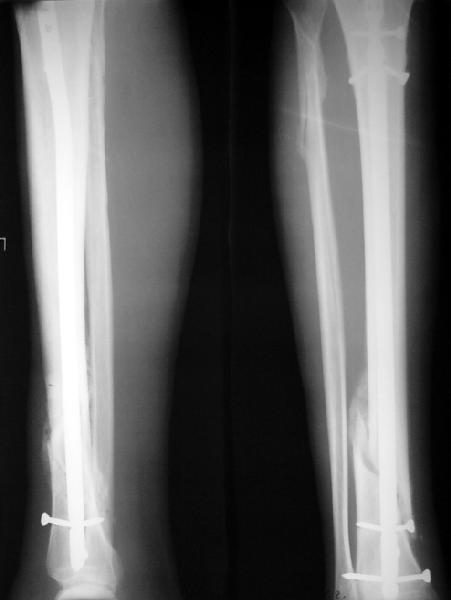

На мой взгляд, на снимках, приведённых Вами - неправильно сростающийся перелом дистальной трети большеберцовой кости, состояние после остеосинтеза интрамедуллярным гвоздём.

Как Вы пишите снимок под номером 1 - менсяц после операции, под номером 2- два месяца после операции.

Установка с медиальной стороны гвоздя в области дистального фрагмента дополнительного шурупа помогло бы Вам репонировать и удержать перелом в анатомическом положении, предотвратило варусную деформацию и смещение по ширине.

На мой взгляд внутрикостная фиксация переломов дистальной и проксимальной трети большеберцовой кости, за исключением поперечных, не очень хорошее решение вопроса, аппарат Илизарова или Тэйлора, позволяющие призвести закрытую анатомическую редукцию и отличное удержание отломков в период сращения.

Да, конечно. Но сочли, что и достигнутое положение приемлемо. Тем более, для non-compliant и low demanding пациента.

А если вспомнить лечение аналогичных повреждений функциональными брэйсами (Sarmiento), там рентгенограммы могут быть еще менее привлекательными, однако результаты вполне приемлемы.

Конечно, чем ближе перелом к суставу, тем больше стрелка нашего "компаса" поворачивает в сторону аппарата. Но все же этот перелом - далеко не самый дистальный, который может быть с успехом вылечен на гвозде. Ну и, как Вы знаете, аппарат у недисциплинированных больных может не только не решить имеющиеся, но и создать новые проблемы.